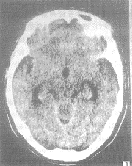

2.1 小脑蚓部实质型血管母细胞瘤4例 当地CT平扫肿瘤接近等密度,加上伪影干扰肿瘤本身显示不清。但有不同程度的脑室受压、移位,第三脑室扩大(图1)。其中1例漏诊达21个月之久,最后一次CT扫描出现明显第三脑室和侧脑室扩大,误诊为脑萎缩。本院CT和MR扫描均清楚显示肿瘤(图2),并诊断为血管母细胞瘤。虽然CT平扫肿瘤接近等密度,但注射造影剂后肿瘤明显增强。在MR扫描时肿瘤T1W呈稍低信号,T2W呈稍高信号,并且明显增强。

图1 小脑蚓部实质性血管母细胞瘤,三脑室扩大